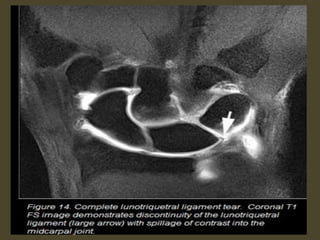

VISI with luno-triquetrum ligament tear and volar tilting of the lunate.

VISI deformity secondary to Lunotriquetral ligament tear.